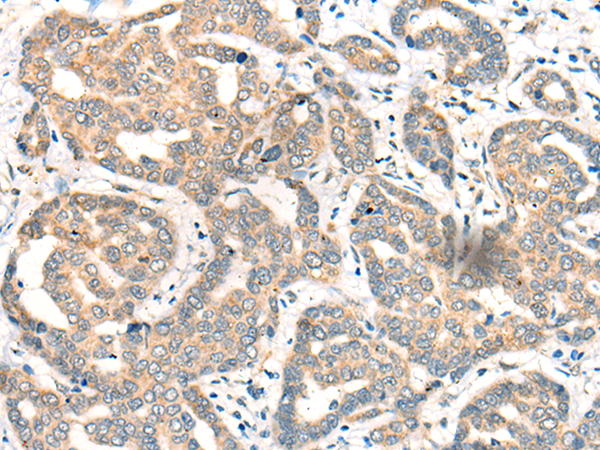

分类: 科研抗体货号: P09492别名: CGR11应用: IHC反应种属: Human